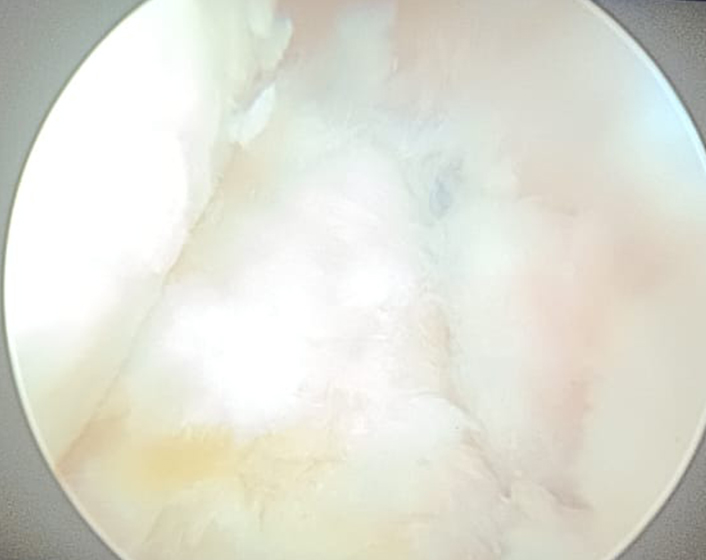

Treatment for a meniscal injury depends on the severity and location of the tear, as well as the patient’s activity level. For minor tears, non-surgical options such as rest, ice, compression, and elevation (RICE), along with physical therapy, can help reduce pain and improve knee function. Physical therapy focuses on strengthening the muscles around the knee to restore stability and mobility. For more severe tears, especially those causing significant pain or locking of the knee, surgical intervention may be necessary. Arthroscopic surgery is commonly used to either repair or remove the damaged portion of the meniscus. In young patients arthroscopic repair is preferred as removal of part or full meniscus increases chances of Osteoarthritis in long term .Post-surgery rehabilitation is crucial for a full recovery and to prevent future injuries.